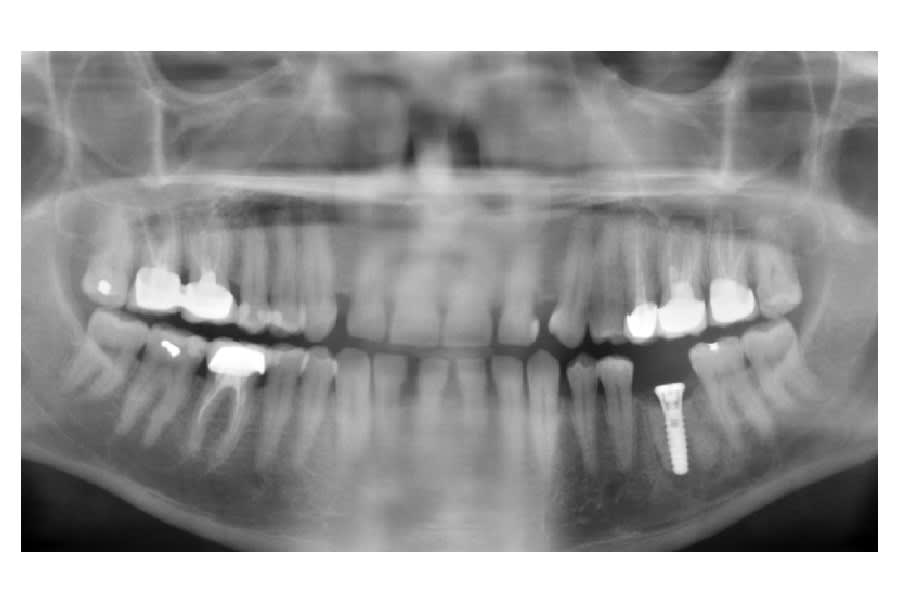

vu ce matin ce patient avec cet implant posé il y a 18 mois

par un confére,j'ai cru que c'étaient les racines que l'on voyait,mais je pense plutôt pour un comblement qui n'est pas trés réussi,quelle est la marque de l'implant et pensez vous qu'il est viable

ci aprés pano et retro

oui c'est bien un straumann...certainement en 4.1mm

les radios sont pas très très bonnes...çà peut aussi être un Zimmer swissplus...

c'est de toutes façons le même type de connexion octogonale...

Sur les Straumann, l'apex est plus arrondi, les spires plus espacées...

C'est pas un Straumann.

Le tissue Level a effectivement des spires plus espacées et l'apex est rond.

De plus,le col est plus en pavillon de trompette.

dis donc, il a gardé les racines de la 36 ou je dois changer de lunettes? parce que là je vois nettement les deux racines sur la pano....

c'est du zimmer swissplus dans du comblement

C'est une copie straumann avec connexion straumann donc c'est bon l'affaire est réglée.

C'est parce que c'est probablement une EII avec l'implant dans le septum et un comblement des espaces laissés par les racines.